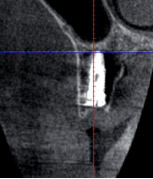

![]() |

術後のCTです。理想的なポジションにインプラントがはいりました。 |